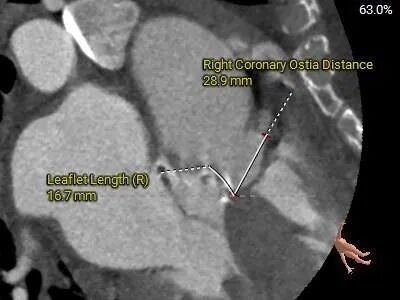

术前CT评估

Type0型二叶式主动脉瓣,LVOT偏敞口型,非横位心。

重度钙化,HU 850积分1711mm3。

左冠18.8,右冠19,综合分析冠脉阻挡风险适中。

瓣上多平面分析。

•左、右冠高度可,切线位测量,无冗长瓣叶,结合瓦氏窦、STJ内径综合预估,冠脉阻塞风险适中,